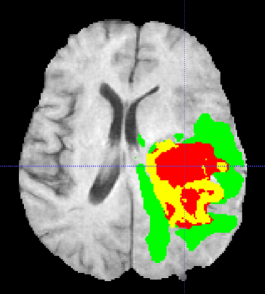

Automated segmentation of brain tumors from 3D magnetic resonance images (MRIs) is necessary for the diagnosis, monitoring, and treatment planning of the disease. Manual delineation practices require anatomical knowledge, are expensive, time consuming and can be inaccurate due to human error. Here, we describe a semantic segmentation network for tumor subregion segmentation from 3D MRIs based on encoder-decoder architecture. Due to a limited training dataset size, a variational auto-encoder branch is added to reconstruct the input image itself in order to regularize the shared decoder and impose additional constraints on its layers. The current approach won 1st place in the BraTS 2018 challenge.